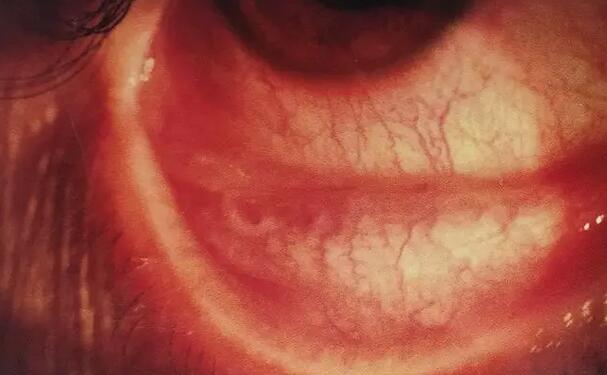

据了解,邹大哥曾在几家医院均被诊断为白内障,建议他等看不见时再手术。“还好,听说厦门眼科中心在漳州开了家分院,我在家人的陪同下到厦门眼科中心漳州眼科医院诊治。”门诊吴强主任发现其右眼视力0.1,眼内已有铁锈症,让厦门眼科中心的陈燕主任会诊,经院内世代的 设备检查,明确诊断后入院医治。陈燕主任为患者做了白内障超声乳化联合晶体植入,并通过玻璃体切割,清除眼内铁锈混浊的玻璃体,将眼球内2MM磁性异物取出,联合眼内光术,一*次性完成手术。

邹大哥手术非常 ,术后右眼视力0.8。“都怪我自己不重视,才让病情更严重。现在右眼能够清晰的看事物了,真的非常感谢陈燕主任和漳州眼科医院的医务人员精心医治护理,让我右眼重见光明”。